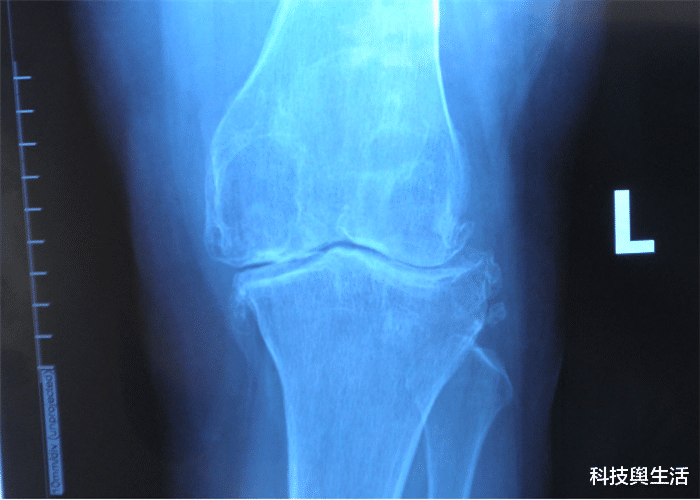

它主要位于哺乳动物的膝盖骨 , 很多灵长类动物都有 , 例如猩猩、猴子 , 它们与人类的一切高度相似 , 都拥有法贝骨 , 只是这一器官的功能较小 , 长期以往便慢慢退化了 , 所以人类彻底抛弃了法贝骨 。 在19世纪的时候 , 已经有11%的人再次拥有法贝骨 , 直到2019年 , 科学家再次发现了不对劲 , 如今拥有法贝骨的人已经占到40% , 再这样持续下去 , 几乎每个人将再次拥有这一大器官 , 那么它的出现到底是好是坏呢?

不少人对法贝骨浮想联翩 , 有人认为它的出现未必是一件好事 , 也有人认为和人类的运动有关 , 很多人平时喜欢跑步、健身等等 , 长期的运动促使法贝骨的出现 , 它能够增强关节力量 , 还能避免不少的摩擦 , 很大程度上保护人类的膝盖 , 法贝骨的出现完全契合这种发展的趋势 。 每个人对法贝骨都表达不同的看法 , 到目前为止 , 法贝骨并没有出现排斥反应 , 也没有对人的身体有太大的影响 , 可见它对人体并没有伤害 , 或许它的再次出现就是保护人类的身体 。